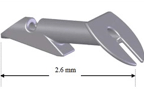

最近では白内障同時の極低侵襲緑内障手術 iStent手術(右)が保険診療で手術ができるように認定されました。

その他CTR手術(左)・瞳孔形成術・眼内レンズ入替術・裂孔閉鎖術・Add-onレンズ挿入術・眼内レンズ回転術など手術をいろいろなデバイスや術式で行っております。